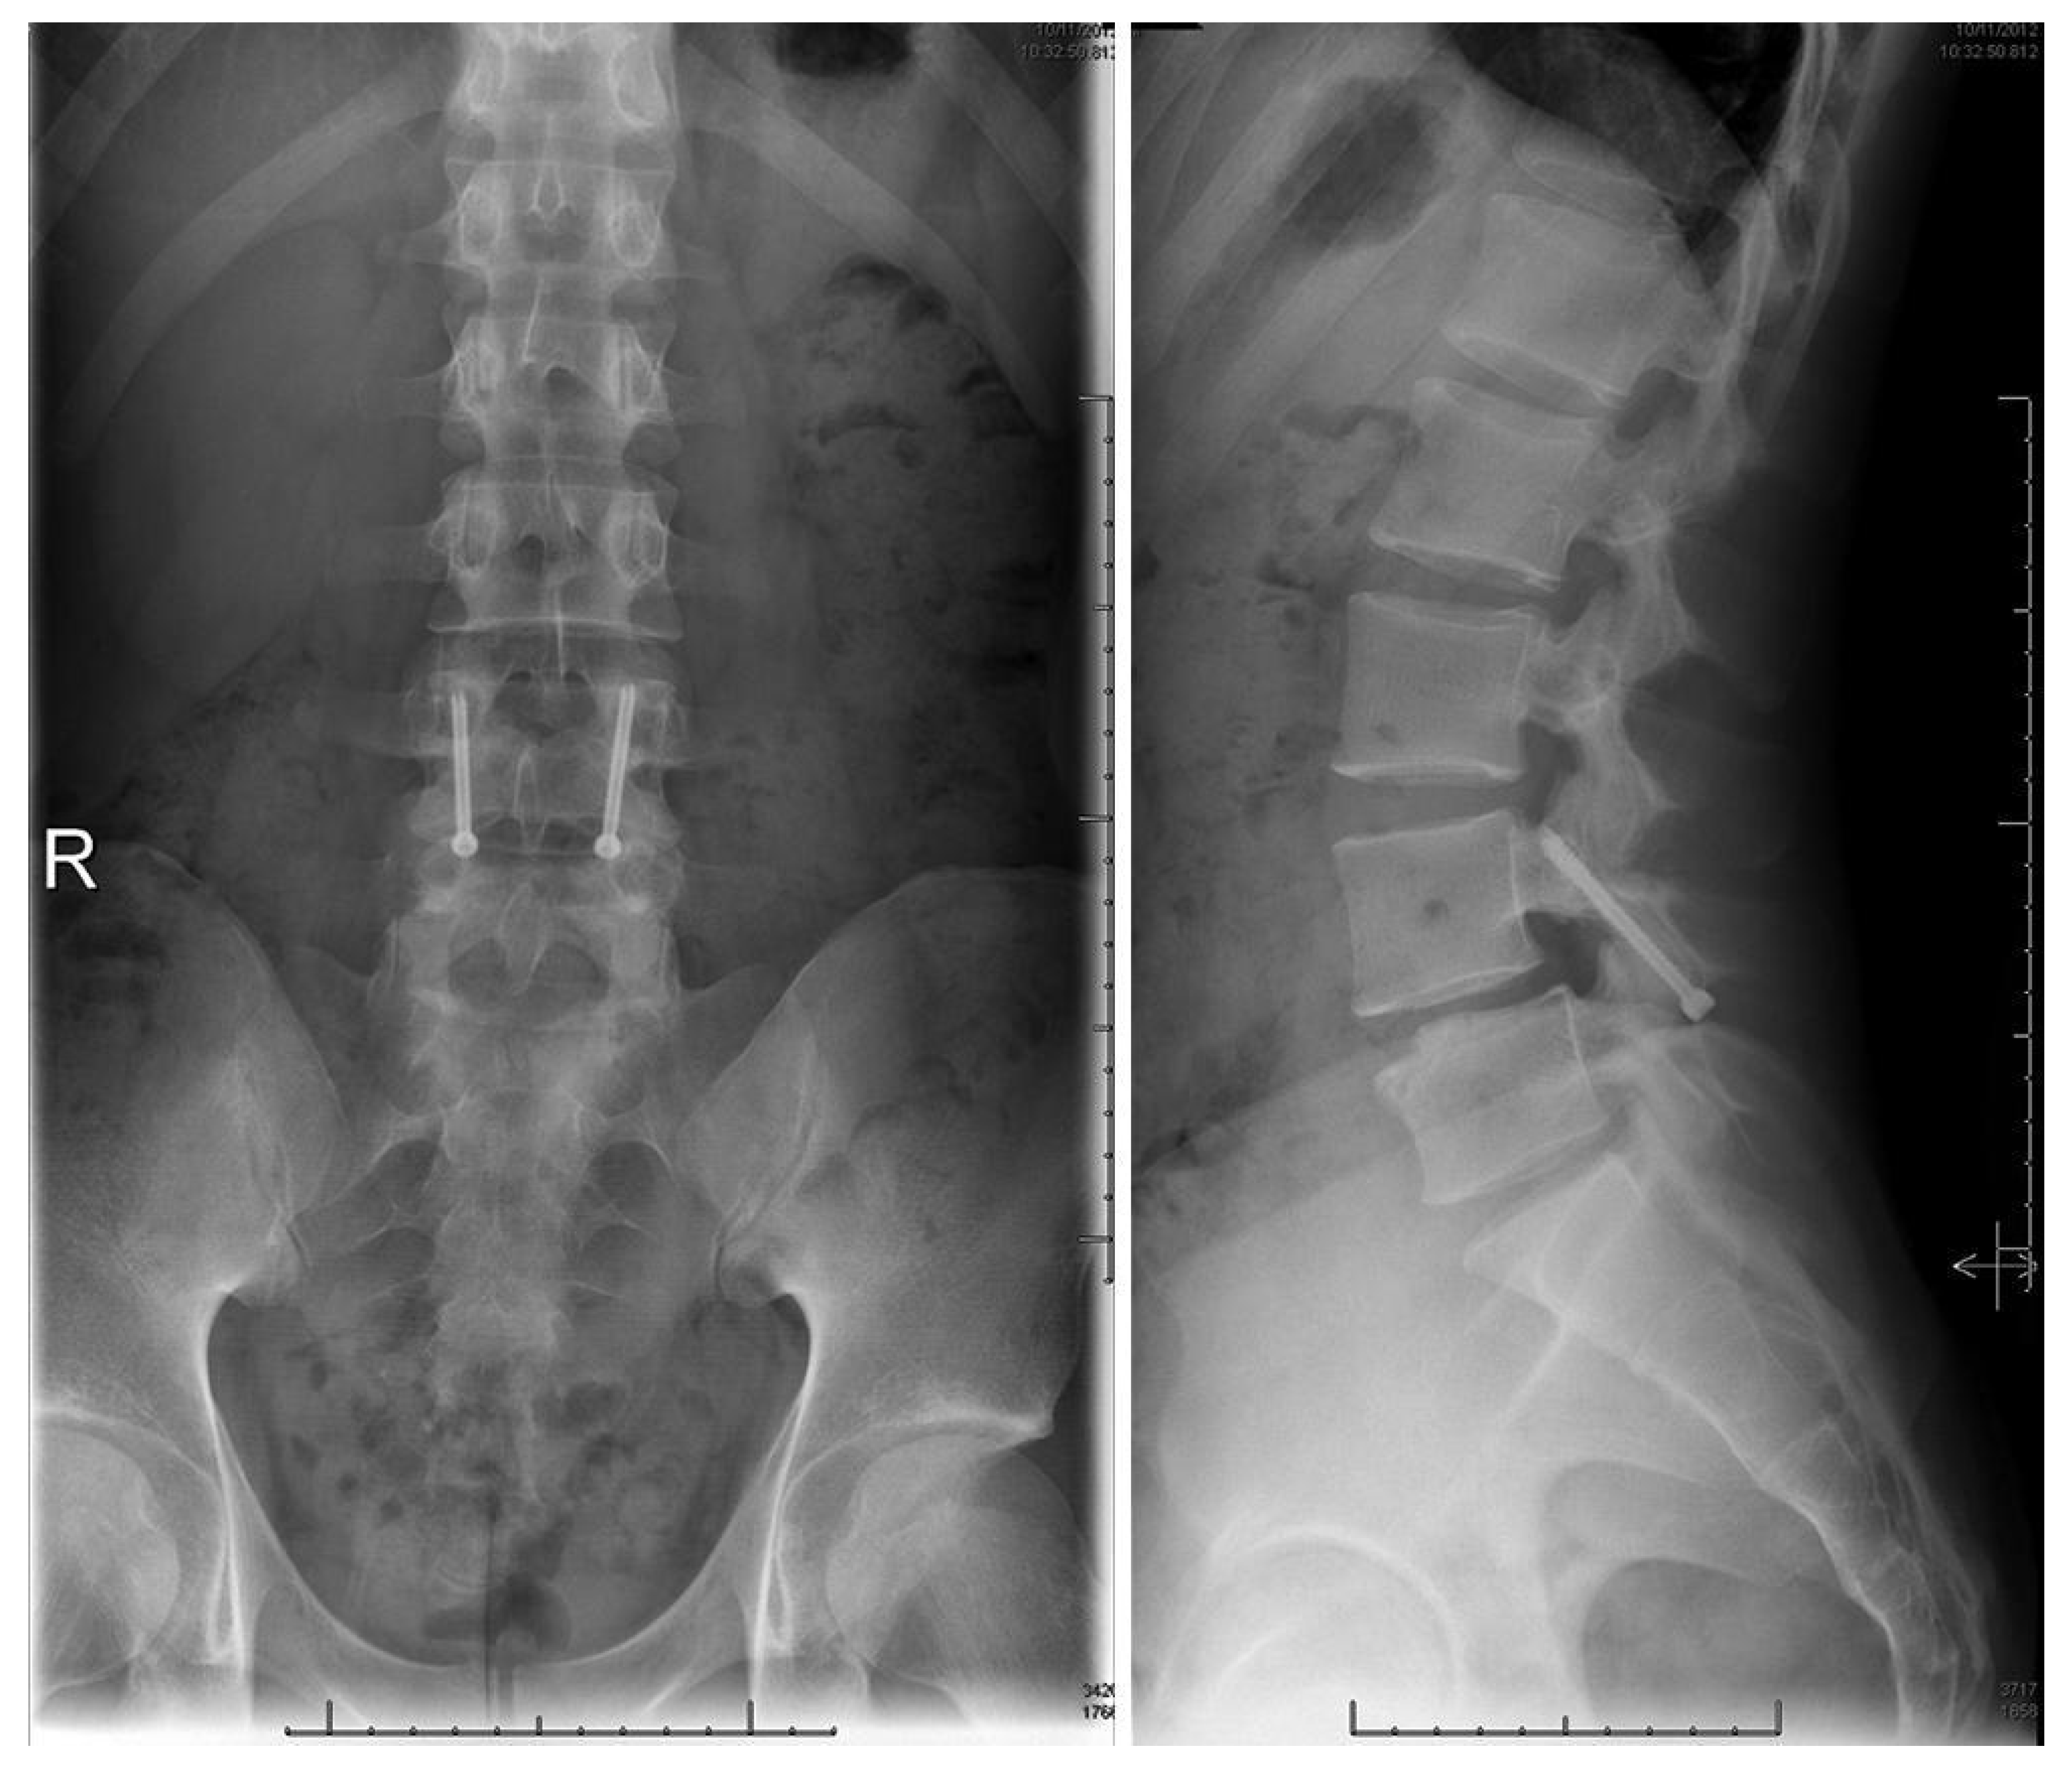

Levi Technique—Minimally Invasive Direct Pars Screw Placement

- Widi, G.A.; Williams, S.K.; Levi, A.D. Minimally invasive direct repair of bilateral lumbar spine pars defects in athletes. Case Rep. Med. 2013, 2013, 659078. [Google Scholar] [CrossRef]

- Ghobrial, G.M.; Crandall, K.M.; Lau, A.; Williams, S.K.; Levi, A.D. Minimally invasive direct pars repair with cannulated screws and recombinant human bone morphogenetic protein: Case series and review of the literature. Neurosurg. Focus 2017, 43, E6. [Google Scholar] [CrossRef] [PubMed]